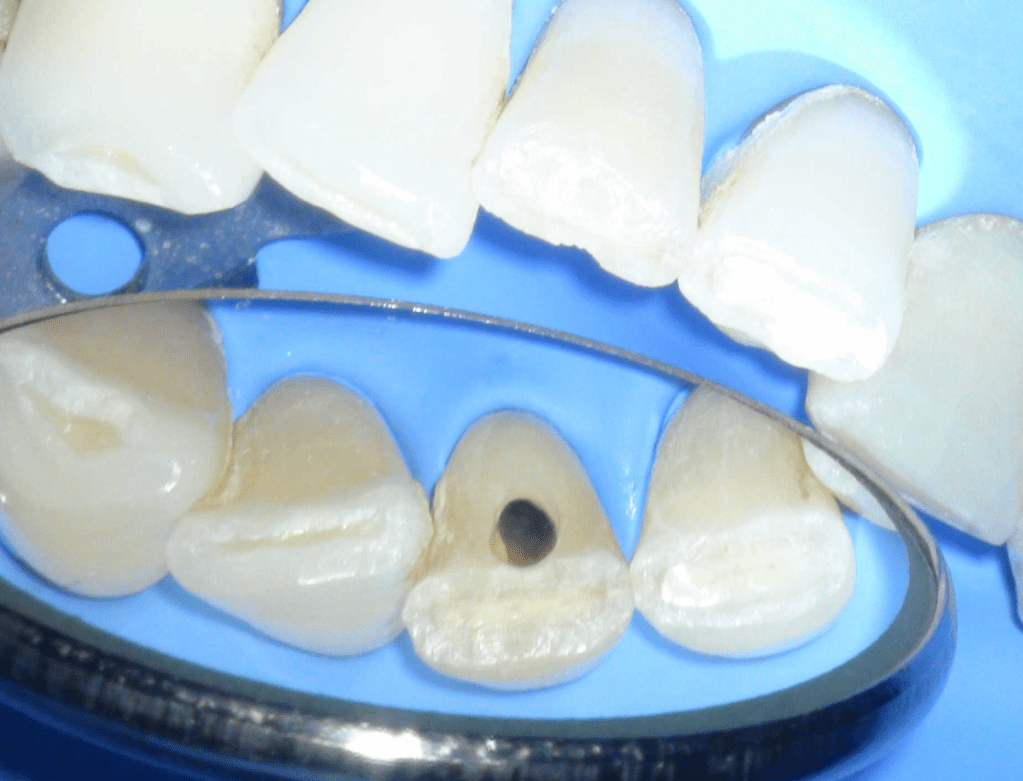

Fistula, dent in dente